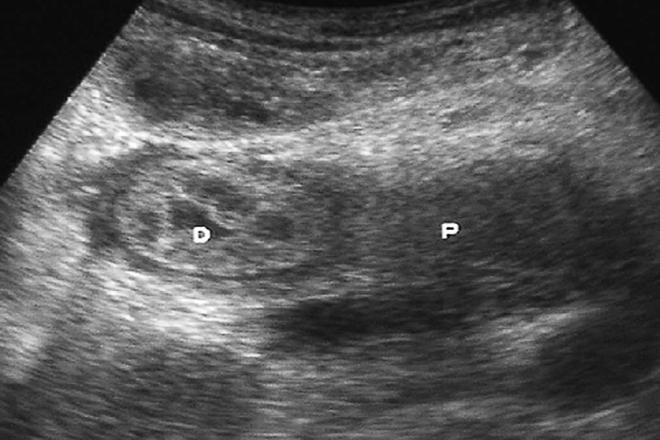

Utilidad de la biopsia transendoscópica guiada por ultrasonido en el diagnóstico de cáncer de páncreas

El diagnóstico de cáncer  de páncreas  se  realiza  generalmente  en  fases  avanzadas, ya que  no produce  síntomas  en etapas  tempranas . uno de los  métodos  para  diagnóstico  en sospecha clínica  de  carcinoma  es  la  biopsia  guiada  por   TC , el cual  es un procedimiento inocuo con buena  sensibilidad  y especificidad , sin embargo  se  asocia  a  siembra  de  células  neoplásicas  en cavidad  peritoneal  y piel, la cual  se  puede  evitar  con la biopsia transendoscópica guiada  por  ultrasonido.

Este procedimiento utilizado  desde 1992  en EU  y países  europeos , para  demostrar la  estirpe  histológica  gastrointestinal  pero  poco  usada en tumores pancreáticos , es un método  útil  para obtención de  tejido  incluso  en lesiones  pequeñas  y difíciles  de localizar , este método  muestra  alta sensibilidad  y especificidad  con escasas  o nulas  complicaciones, las  más comunes  son pancreatitis  aguda y hemorragias  en menos  del 2% , permite  evaluaciones  estructurales  y citológicas, comparados  con los procedimientos que  solo  permiten estudio citológico. El propósito  de  este trabajo es  evaluar  los  cambios  de  diciembre del 2006  con cuadro clínico compatible  con cáncer de páncreas además  de  biopsia  transendoscópica  guiada  por  ultrasonido,

Se revisaron 46  biopsias  transendoscópicas  guiadas  por ultrasonido  evaluando patrones  del epitelio ductal  como  glándulas  con bordes  irregulares, glándulas  incompletas o fragmentadas , glándulas  cribiformes, grupos  de  células  epiteliales  en  grupos  sólidos  o células epiteliales  individuales  con pérdida de  cohesión, los criterios citológicos fueron : nucleomegalia , cromatina  grumosa , aumento  de  relación núcleo citoplasma, atipia , pleomorfismo , membrana nuclear irregular, nucléolo  prominente , pérdida de la  polaridad, pseudoinclusiones  nucleares , núcleo  vesiculoso , sobreposición nuclear , mitosis  anormales  atípicas, células multinucleadas ,canibalismo, células  mucoproductoras  con mucina intracelular o extracelular  y diferenciación  fusiforme , escamosa o   endocrina, otros  parámetros   fueron  necrosis  coagulativa  , necrosis  grasa  , fibrosis , desmoplasia , epitelio  ductal , acinar  o ambos  , inflamación aguda , invasión  neural perineural, linfovascular o  ambas,  los casos  se agruparon en dos  categorías iniciales: biopsia  suficiente  para  el  diagnóstico  y la biopsia  no concluyente   para  diagnóstico , las  biopsias  con material  adecuado  se clasificaron en  dos categorías : lesiones  benignas  y cáncer